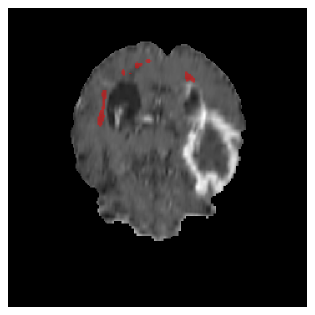

Appendix A Qualitative results

Figure 5 illustrates the segmentation evolution for the same BRATS patient in S2 sequence. The key difference here is that the best buffer-free strategy is EWC (=1), and training on BRATS data starts from episode 2 instead of episode 1 as BRATS is encountered at episode 2 in S2. The cumulative approach retains segmentation across episodes but continues to generate false positives, which become even more pronounced in the final episode. The naive approach, lacking a CL mechanisms, completely overrides previous knowledge, leading to failed segmentation in later episodes. EWC (=1) approach initially maintains segmentation but experiences a sharp decline in episode 4, where it fails to segment the tumor. In the final episode, it undersegments the lesion, missing a significant portion of the tumor. In contrast, the proposed approach consistently preserves segmentation across episodes. While initially introducing false positives, it gradually refines predictions, retaining the tumor region while minimizing misclassifications. It maintains clear tumor delineation by the final episode, demonstrating effective knowledge retention and adaptability throughout training.